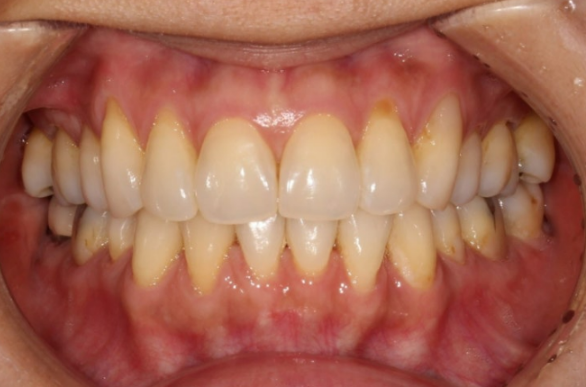

23.08

이 후 2개월 간 마무리 치료를 더 하고 재교정치료를 마쳤습니다.

총 치료기간은 4개월 입니다.

23.04~23.08

치간삭제와 고무줄을 병행하면서 튀어나와있었던 앞니를 뒤로 꽤 많이 넣었습니다.

철사 유지장치까지 이물감 없이 깔끔하게 들어간 모습입니다.

유지장치도 주기적인 관리가 필요합니다.

이번에는 정기검진과 유지관리를 더욱 철저히 받기로 하셨습니다.

앞니 두개가 유난히 커보이던 문제도 깔끔히 해결이 되었습니다.